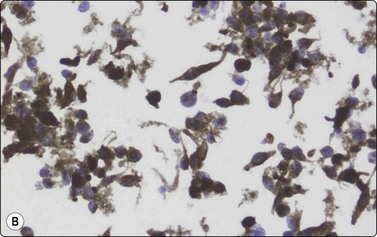

Merkel cell carcinoma (neuroendocrine carcinoma of skin) (Fig. 14.17, and see Fig. 5.23)61,62

image

Fig. 14.17 Merkel cell carcinoma

(A) Poorly cohesive cells; nuclear pleomorphism and some molding, scanty blue cytoplasm resembling lymphoid cells (MGG, HP); (B) Cellular smear of dispersed small cells with round, dark nuclei (Pap, HP); (C) Dot-like positive staining with CAM5.2 (immunostaining, HP).

Criteria for diagnosis

Cell-rich smears of mainly dispersed small neoplastic cells,

Fragile, scanty, blue (MGG) cytoplasm; high nuclear : cytoplasmic ratio; many stripped nuclei,

Clustered cells may show nuclear molding and rosette-like grouping,

Round or ovoid, mildly to moderately irregular hyperchromatic nuclei with inconspicuous nucleoli,

Mitoses frequent,

Lymphoid globules (lymphoglandular bodies) absent,

Dot-like paranuclear staining for cytokeratin; chromogranin usually positive.

Primary neuroendocrine carcinoma of skin is an uncommon neoplasm, mainly seen in elderly patients and most often in the head and neck. It is locally aggressive and often metastasizes to regional lymph nodes. Clinically and cytologically, Merkel cell tumor can be difficult to distinguish from non-Hodgkin lymphoma when it presents as lymphadenopathy without an obvious primary, as is often the case (see Chapter 5).

Page 379

Smears are usually highly cellular. The cells are mainly dispersed but some are clustered or form single files with nuclear molding and sometimes rosette-like groups. The main differential diagnoses are lymphoma and metastatic small cell carcinoma. Amelanotic melanoma may also be considered. The absence of lymphoid globules in the background and subtle differences in nuclear chromatin help in this distinction. Staining for CAM5.2, CK7 and CK20 demonstrates characteristic dot-like intracytoplasmic deposits in the tumor cells (Fig. 14.17C), and staining for neuroendocrine markers is usually positive. Electron microscopy shows well-demarcated whorls of cytoplasmic filaments.